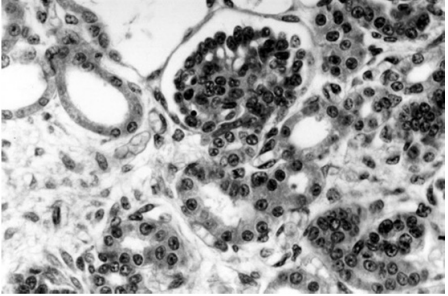

O tecido hematopoiético é um tipo de tecido conjuntivo responsável pela produção de células sanguíneas e da linfa. Nas figuras abaixo estão representadas algumas células que fazem parte do tecido hematopoiético.

Assinale a opção em que há correta correspondência entre a célula representada em cada uma das figuras precedentes e o seu respectivo tipo.